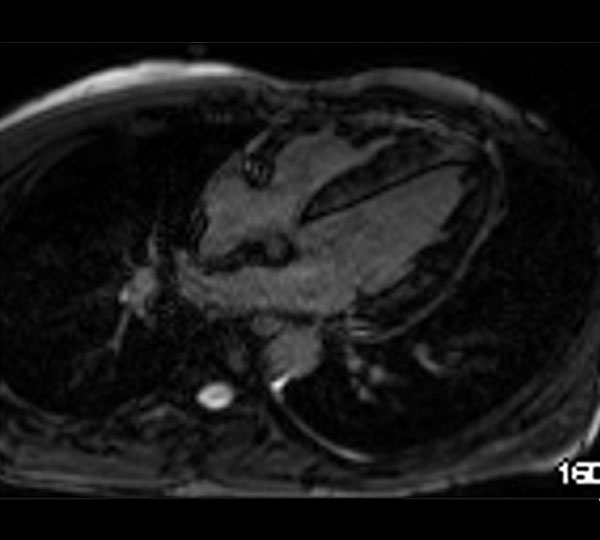

- IRM myocardique : Cardiopathie hypertrophique gauche à prédominance septale. SIV 14 mm et PPVG 12 mm ; masse 106 mg/m² non dilaté 88 mL/m². Pas d’anomalie VD

➔ Anomalie claire gadolinium patchy diffuse intra-myocardique, évoquant fibrose assez étendue diffuse non systématisée à un territoire coronaire

Figures 5 et 6 : temps de rehaussements tardifs à l’IRM

- IRM myocardique ➔ Mauvaise qualité due à l’atteinte myocardique amyloïde diffuse rendant du fait de l’absence de myocarde sain, difficile le réglage du temps d’inversion pour l’obtention de rehaussements tardifs exploitables.